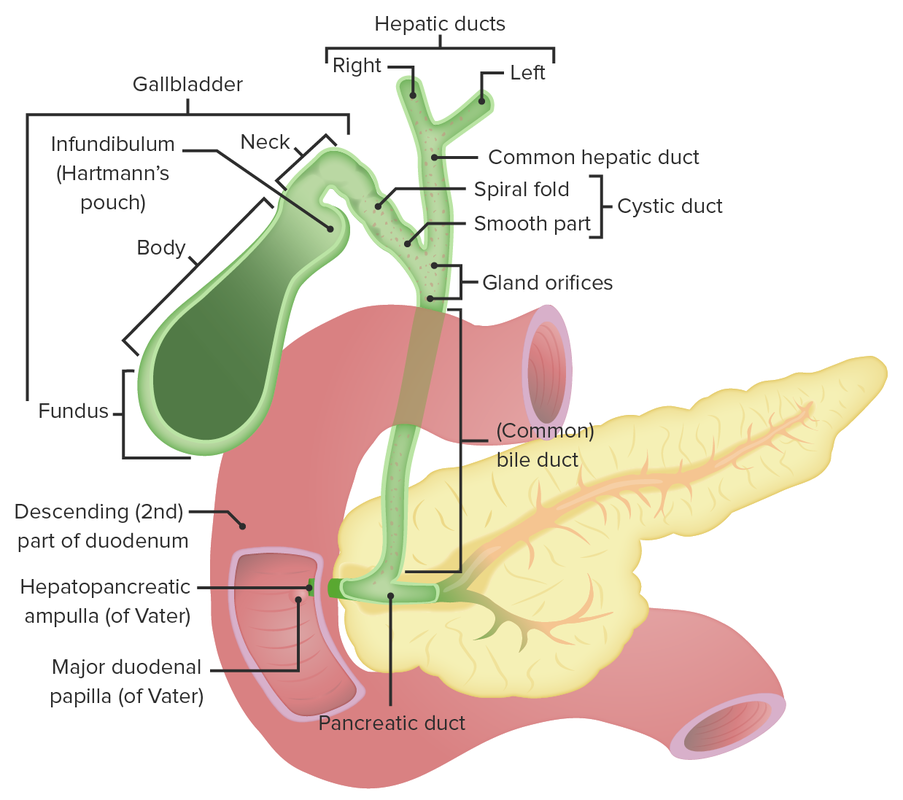

De galblaas. Anatomie van de galblaas en galwegen. Anatomie van de twaalfvingerige darm en de

Anatomy of the gallbladder and bile ducts Surgery Oxford International Edition